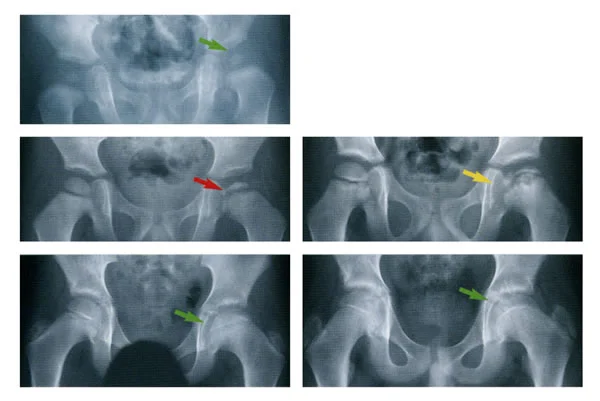

/Legg-Calves-Perthes disease is a condition that often begins in childhood. It occurs when part of the hip joint does not receive an adequate amount of blood supply. When this happens, bone cells begin to die, and the joint deteriorates. As a result, a person may experience pain and gait problems. It can also increase the risk of a person developing osteoarthritis later in life. Legg-Calves-Perthes disease is also known as idiopathic osteonecrosis, ischemic necrosis of the hip, coxa plana, osteochondritis, or avascular necrosis of the femoral head. It is estimated that about one in every 1,200 children have Legg-Calves-Perthes disease.